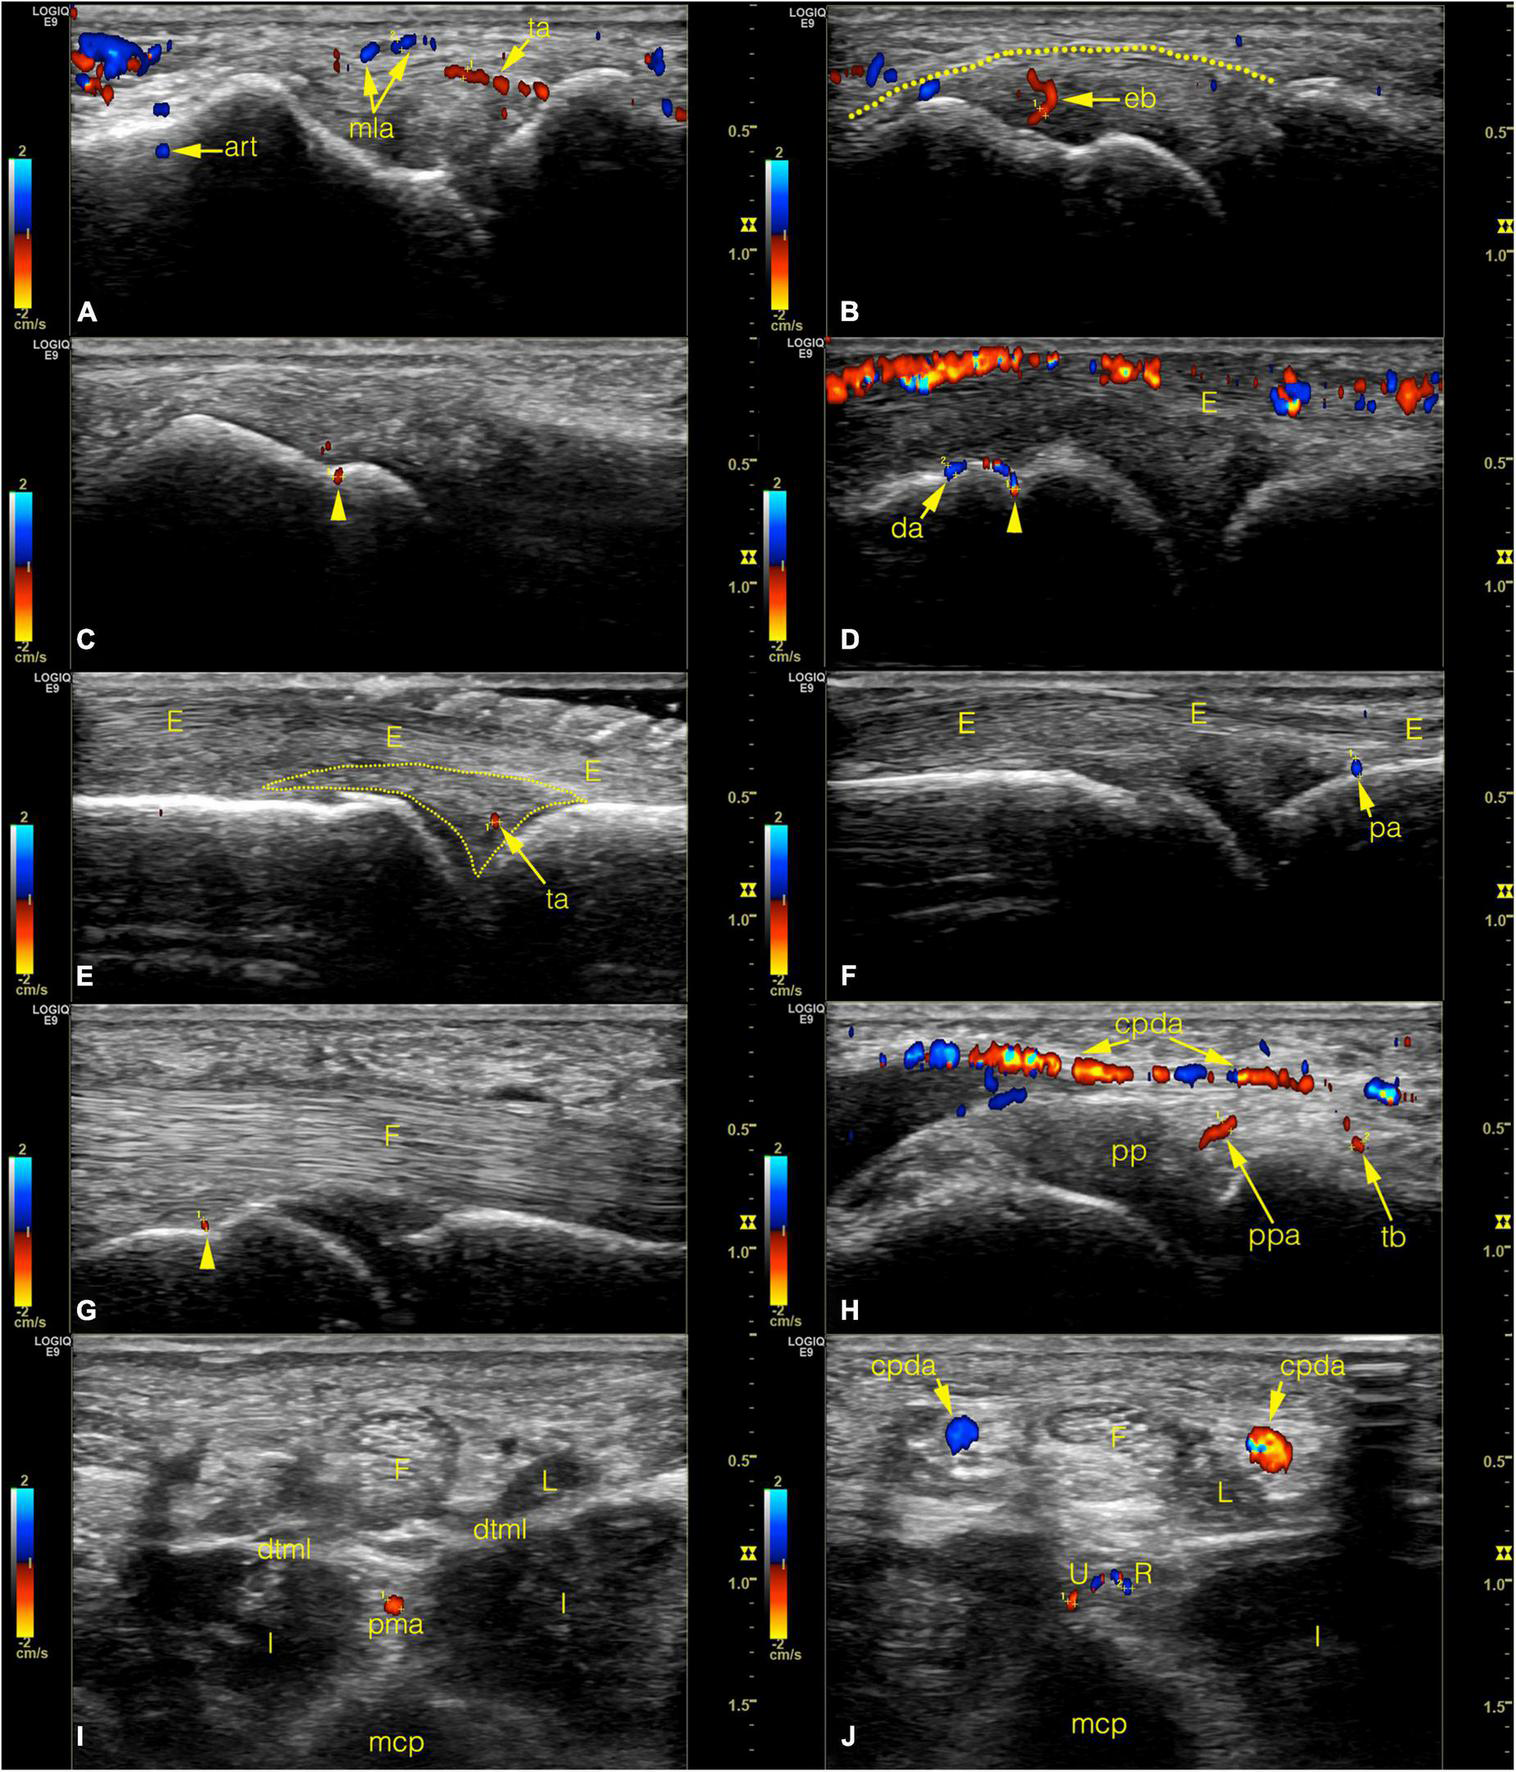

FIGURE 7

Color Doppler ultrasonographic images of normal joint vessels on healthy volunteers. (Left side of the images refers to the metacarpal half.) (A–C) radial side of the 2nd joint on coronal plane. On panel (B) the dotted line indicates the outer border of the enthesis. (D–F) dorsal side of the joint on sagittal plane images. Note the superficial cutaneous vein along the top of panel (D). On panel (E) the dotted line indicates the dorsal triangle. (G,H) palmar side on sagittal plane. (I,J) axial plane images with the homuncule shaped soft tissue complex in the center with palmar metacarpal artery and it’s bifurcation into R- and U-branches, respectively. arrowhead, entry point of a bone supplying vessel; art, Doppler mirror artifact; cpda, common palmar digital artery; da, dorsal arcade; dtml, deep transverse metacarpal ligament; eb, enthesial branch; E, extensor tendon; F, flexor tendon; I, interosseous muscle; L, lumbrical muscle; mcp, metacarpal; mla, main lateral artery; pa, phalangeal arcade; pma, palmar metacarpal artery; pp, palmar plate; ppa, palmar plate artery; ppda, proper palmar digital artery; R, R-branch; ta, triangular arcade; tb, tenosynovial trunk; U, U-branch.

The MCP joints 2–5 of both hands of two males (ages 31 and 59 years, mean 45 years) and eight females (ages 21–76 years, mean 48.25 years) were scanned as described above (section “Scanning method”). Three joints (1 MCP4 and 2 MCP5) were excluded due to technical problems leaving a total of 77 joints examined using color Doppler mode (Table 1 and Figure 7). The number of recorded images of the left hand ranged between 56–238 (average: 146.6) and 78–266 (average: 139.7) on the right hand, respectively. Supplementary Table 2 summarizes the number of joint specimens with Doppler-signal and their diameters. Due to the lack of proper acoustic window no data were registered on the interdigital surfaces of the joints. The most frequent location with detected Doppler signal was the dorsal depression of the metacarpal head (64.94%) (Figure 7D) and the location of the main lateral arteries (68.42%) (Figure 7A). The distal PMA was identified in 53.25% of the joints, typically embedded in a homunculus-shaped connective tissue mass on axial plane images (Figures 4I, 7I). In all other locations, Doppler signal was captured in less than 50% of cases (Supplementary Table 2).